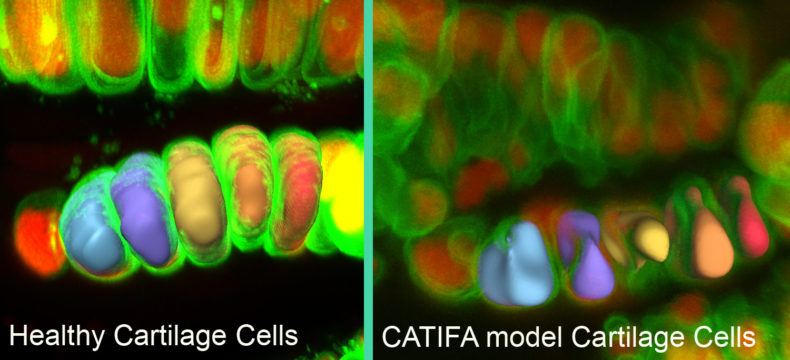

Knapik and her team were exploring the function of a gene called ric1 in zebrafish. They knew that mutation of ric1 disrupted collagen secretion and caused craniofacial and other skeletal defects in fish.

The symptoms of the new disease, CATIFA, can be explained by loss of collagen function, Knapik said. Collagen is the main structural component of the extracellular matrix — the “mortar” between the cellular “bricks.”

Using zebrafish, Knapik and her team were able to determine that the RIC1 protein is part of the cellular machinery that processes and ships collagen out of the cell.

“In the absence of RIC1, you don’t get the collagen shipment, and you don’t have matrix,” Knapik said. “That leads to the broad spectrum of symptoms that we find in the electronic health records of adults and in the children with CATIFA.”